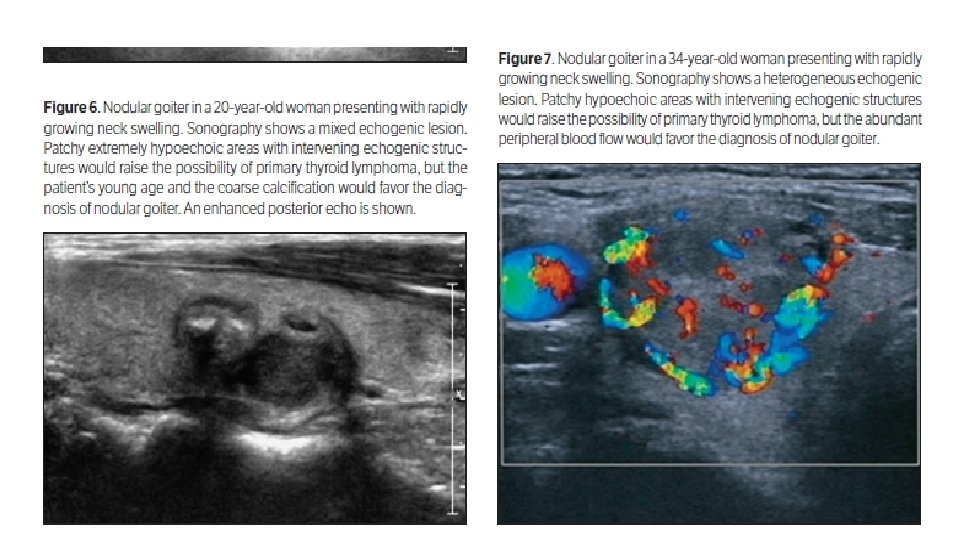

ØWe included 13 consecutive patients with pathologically proven primary thyroid lymphoma at Xiangya Hospital from 2007 to 2013 ØAnother 27 patients were randomly chosen as controls who had pathologically proven nodular goiter at our hospital from 2012 to 2013

Comparison of Clinical and Sonographic Features Between Primary Thyroid Lymphoma and Nodular Goiter